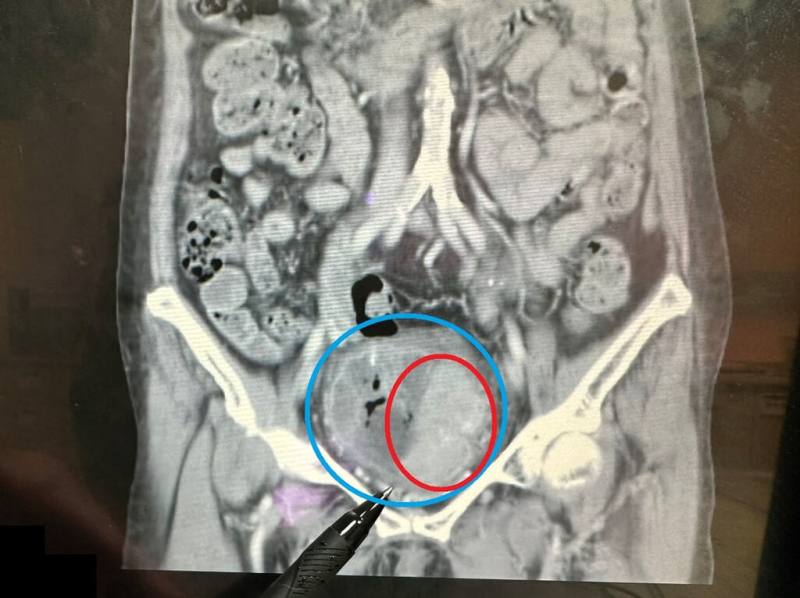

苗栗縣大千綜合醫院17日分享案例,76歲婦人持續近1個月出現無痛性血尿症狀,就醫檢查雖腎功能正常,但膀胱(藍圈處)內有1個約7x6公分的巨大腫瘤(紅圈處)。(大千醫院提供)

(中央社訊)苗栗縣76歲陳姓婦人持續近1個月出現無痛性血尿症狀,就醫檢查雖腎功能正常,但膀胱內竟有1個約7x6公分的巨大腫瘤,經手術清除腫瘤,成功保留膀胱,術後恢復良好定期追蹤。

苗栗縣大千綜合醫院泌尿科醫師陸兆明17日分享這起案例指出,婦人雖有明顯的血尿狀況,但未出現發炎反應、尿路結石、腎水腫或腎腫瘤的情況,且腎功能正常,進一步安排靜脈注射腎盂攝影,發現膀胱內有大片陰影,續以膀胱鏡檢查才揪出腫瘤。

陸兆明表示,婦人的腫瘤體積頗大,已占據未漲尿時的膀胱將近1/2空間,所幸腫瘤細胞尚未侵犯到膀胱外圍,也沒有骨盆淋巴結轉移的情況,適用「經尿道膀胱腫瘤刮除手術」處理。